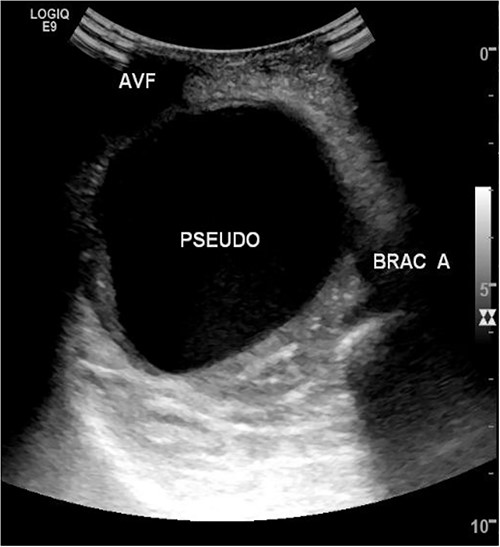

She then re-presented 2 months later with gradually increasing right upper extremity edema with a palpable thrill in the arteriovenous fistula. Duplex identified a large hematoma with patency of the fistula (Fig. 2). A tunneled dialysis catheter was placed to allow the swelling and hematoma to resolve. After medical optimization, the patient consented for operative intervention with the intention to evacuate the hematoma. There was noted to instead be a 20 × 35 cm PSA of the brachial artery (Fig. 3). The median nerve was identified and preserved. After proximal and distal control, the patient was heparinized, and the brachial artery PSA was decompressed with evacuation of large mural thrombi (Fig. 4). This artery segment was resected, and patch angioplasty was performed (Fig. 5). The fistula was ligated, and the distal remnant was preserved. Radial and ulnar pulses were palpable. The patient recovered well postoperatively.

Arteriovenous access hematomas are not uncommon but the presentation of a large brachial artery pseudoaneurysm is very rare. Pseudoaneurysms can be congenital, associated with connective tissue disorders, or due to trauma or iatrogenic causes [2]. Brachial PSAs are rare and occur in <0.04% of cases, but incidence is rising with increased brachial endovascular access [4]. They are estimated to be formed by iatrogenic causes occurring in 0.3% to 0.7% of patients [5, 6]. In our case, the PSA may have been formed during an inadvertent arterial puncture site from dialysis or during previous fistulograms. The PSA was initially assumed to be a hematoma as prior duplex did not show flow into the cavity.

However, this is the first case report describing a truly giant, > 20 × 35 cm, brachial artery pseudoaneurysm from a dialysis patient. Duplex can help evaluate dialysis issues, but as demonstrated by this case, may not accurately identify all access complications or hematomas.